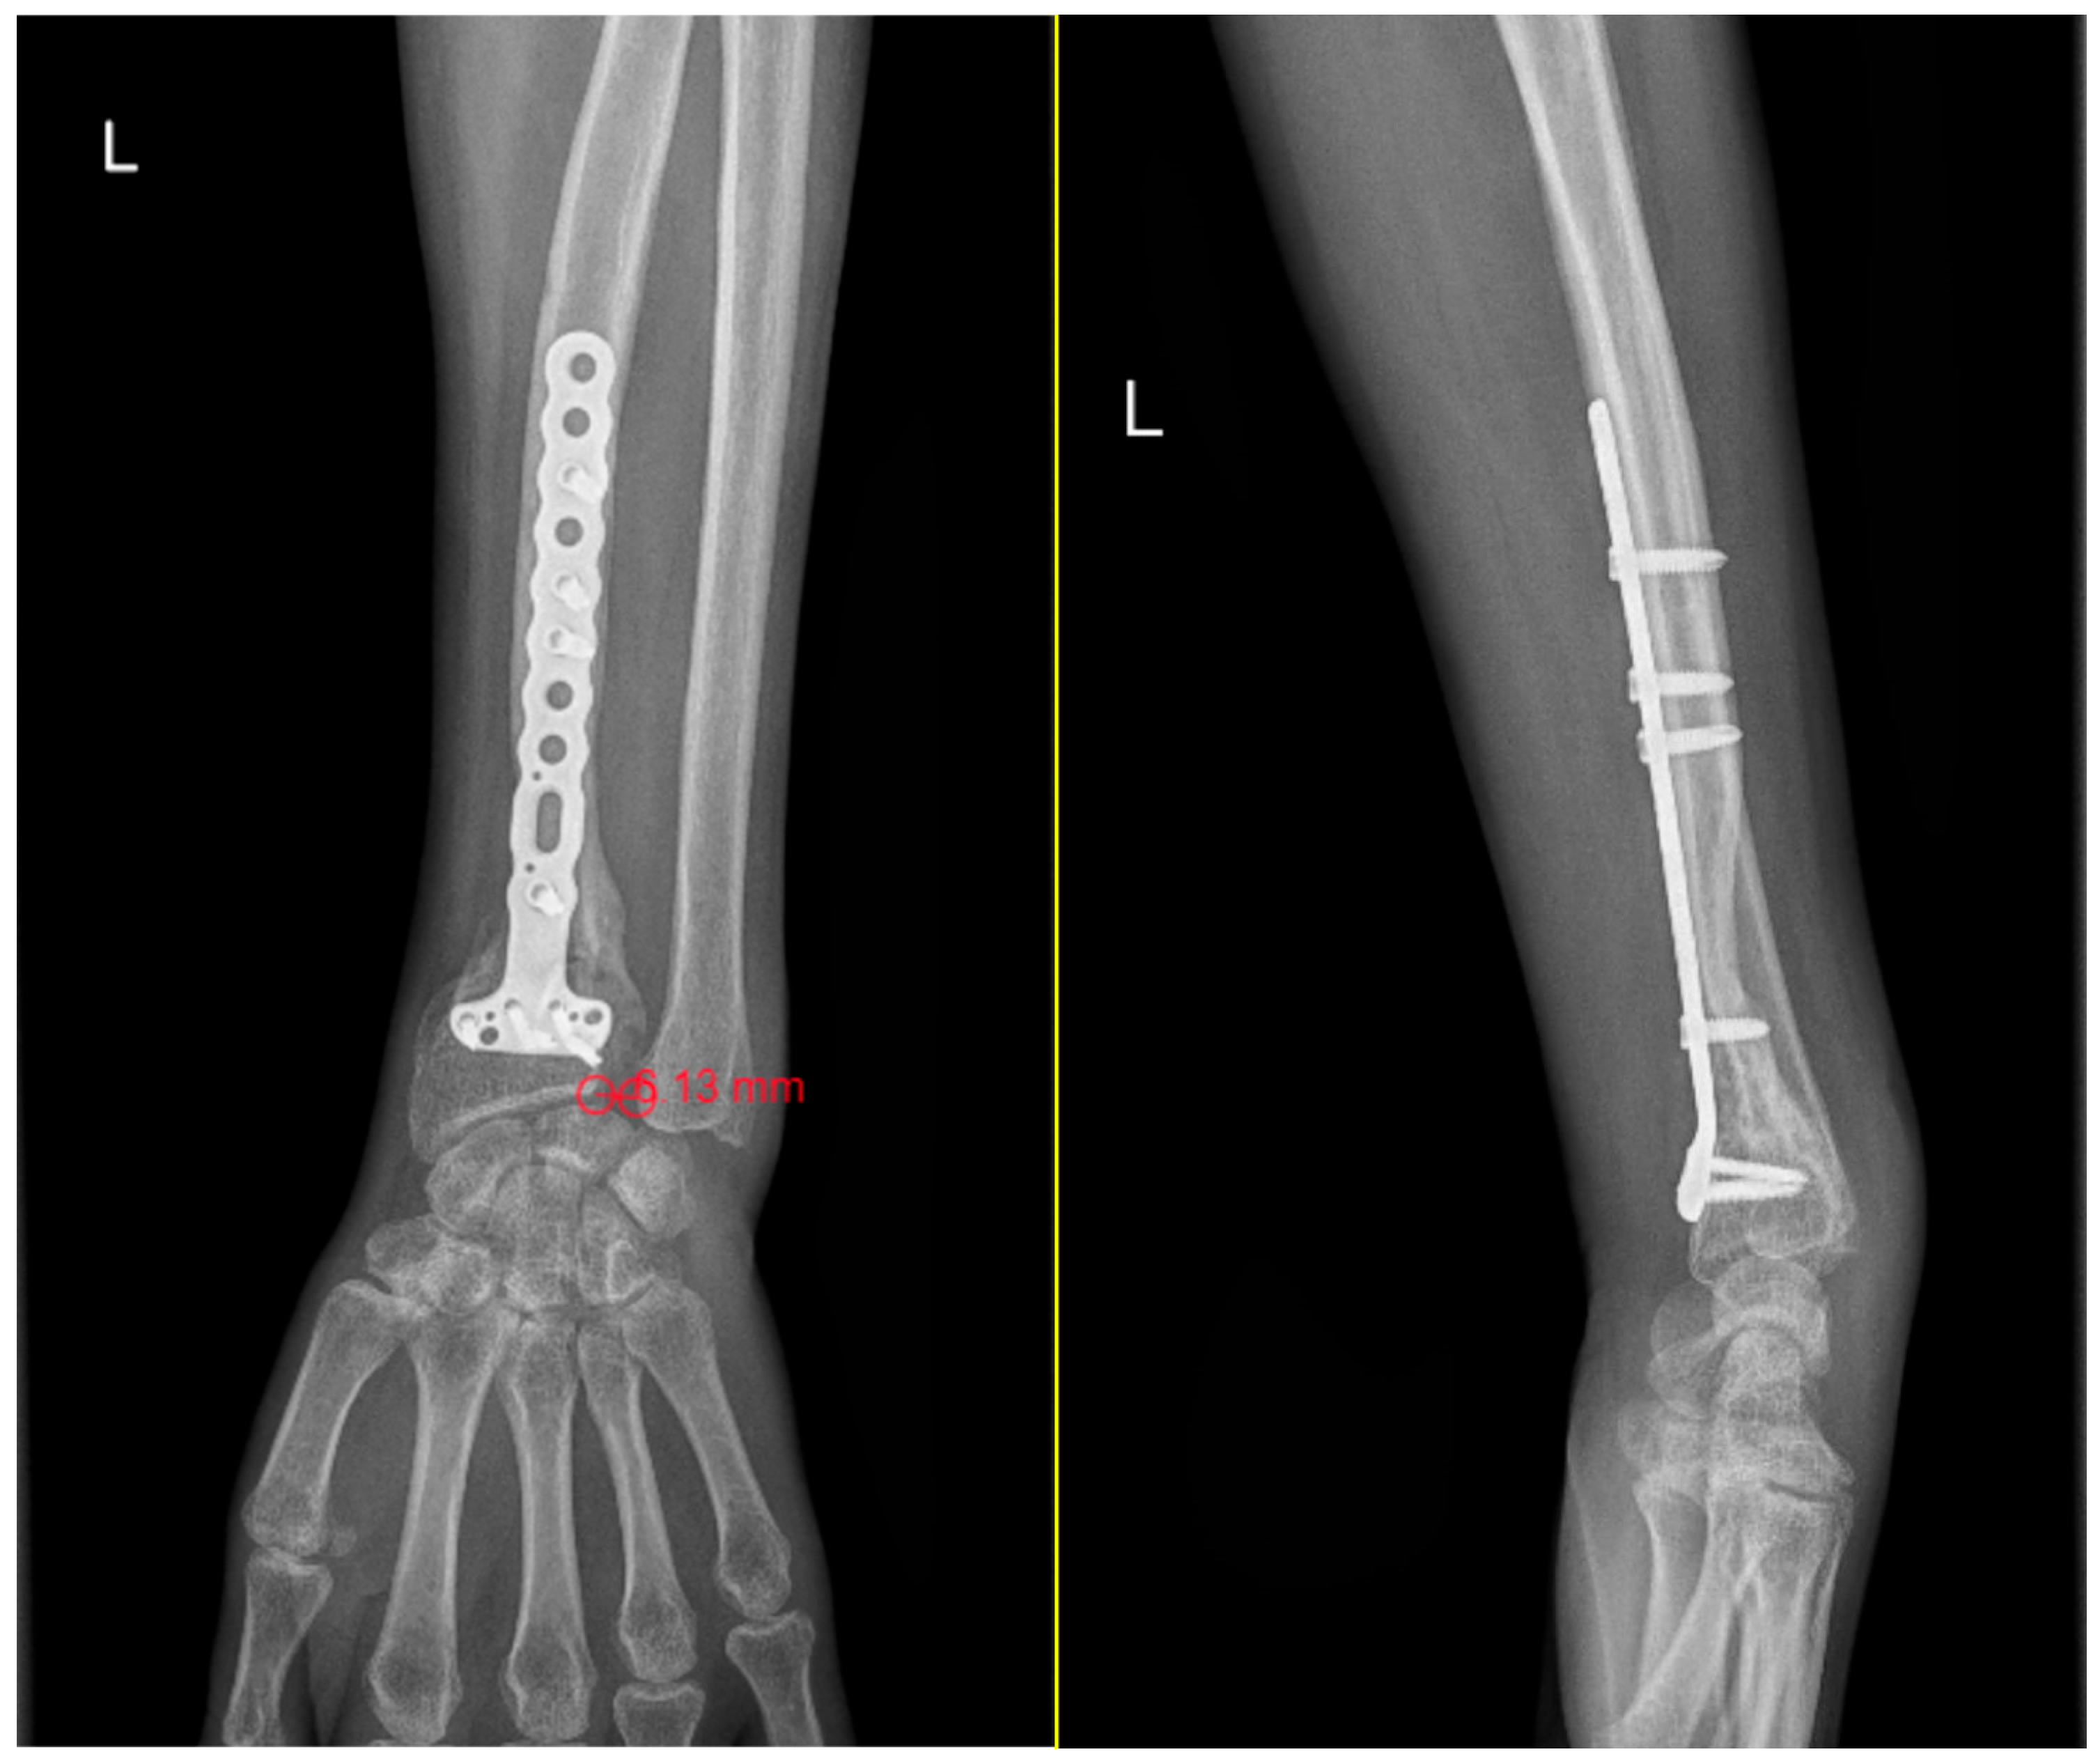

Evaluation criteria DRUJ injuries were classified using a combination of radiological and clinical parameters, with the objective of characterizing the severity of joint instability. From an imaging perspective, three key elements were assessed. The first was the DRUJ distance, with values greater than 5 mm considered suggestive of significant instability (Figure 2) [11,12]. The second was ulnar variance, which was regarded as normal when within ±2 mm [13,14,15]. The third was the orientation of the ulnar head on the lateral radiograph, which was categorized as neutral, dorsally inclined when the projection exceeded 6 mm relative to the radius, or volar inclination [16,17].

Figure 2.

Measurements of DRUJ gap and ulnar variance on standard anteroposterior wrist radiographs. DRUJ distance greater than 5 mm (6.13 mm) following internal fixation of a distal radius fracture with a locked titanium plate. The increased gap is consistent with a grade 3 DRUJ injury, lateral view that shows neutral ulnar head orientation.